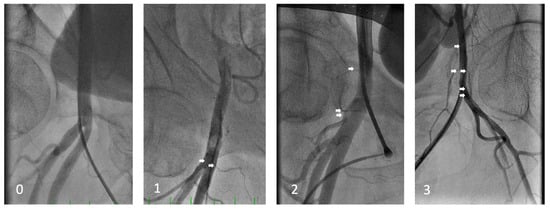

| Femoral | 196 (72.3) | 161 (72.5) | 35 (71.4) | 0.999 |

| Femoral metrics | n = 196 | n = 161 | n = 35 | |

| Minimal femoral diameter (mm) | 7.3 ± 1.5 | 7.6 ± 1.4 | 5.9 ± 1.2 | <0.001 |

| Maximal femoral diameter (mm) | 8.0 ± 1.7 | 8.3 ± 1.6 | 6.5 ± 1.2 | <0.001 |

| Femoral side branches density | 1.2 ± 0.9 | 1.2 ± 0.9 | 1.5 ± 0.8 | 0.054 |

| Mid-femoral head to bifurcation (mm) | 23.5 ± 12.6 | 24.3 ± 12.5 | 19.5 ± 12.5 | 0.048 |

| Bifurcation to femoral head height ratio | 1.01 ± 0.28 | 1.02 ± 0.27 | 0.95 ± 0.30 | 0.197 |

| Puncture to femoral head height ratio | 0.58 ± 0.28 | 0.59 ± 0.26 | 0.54 ± 0.36 | 0.501 |